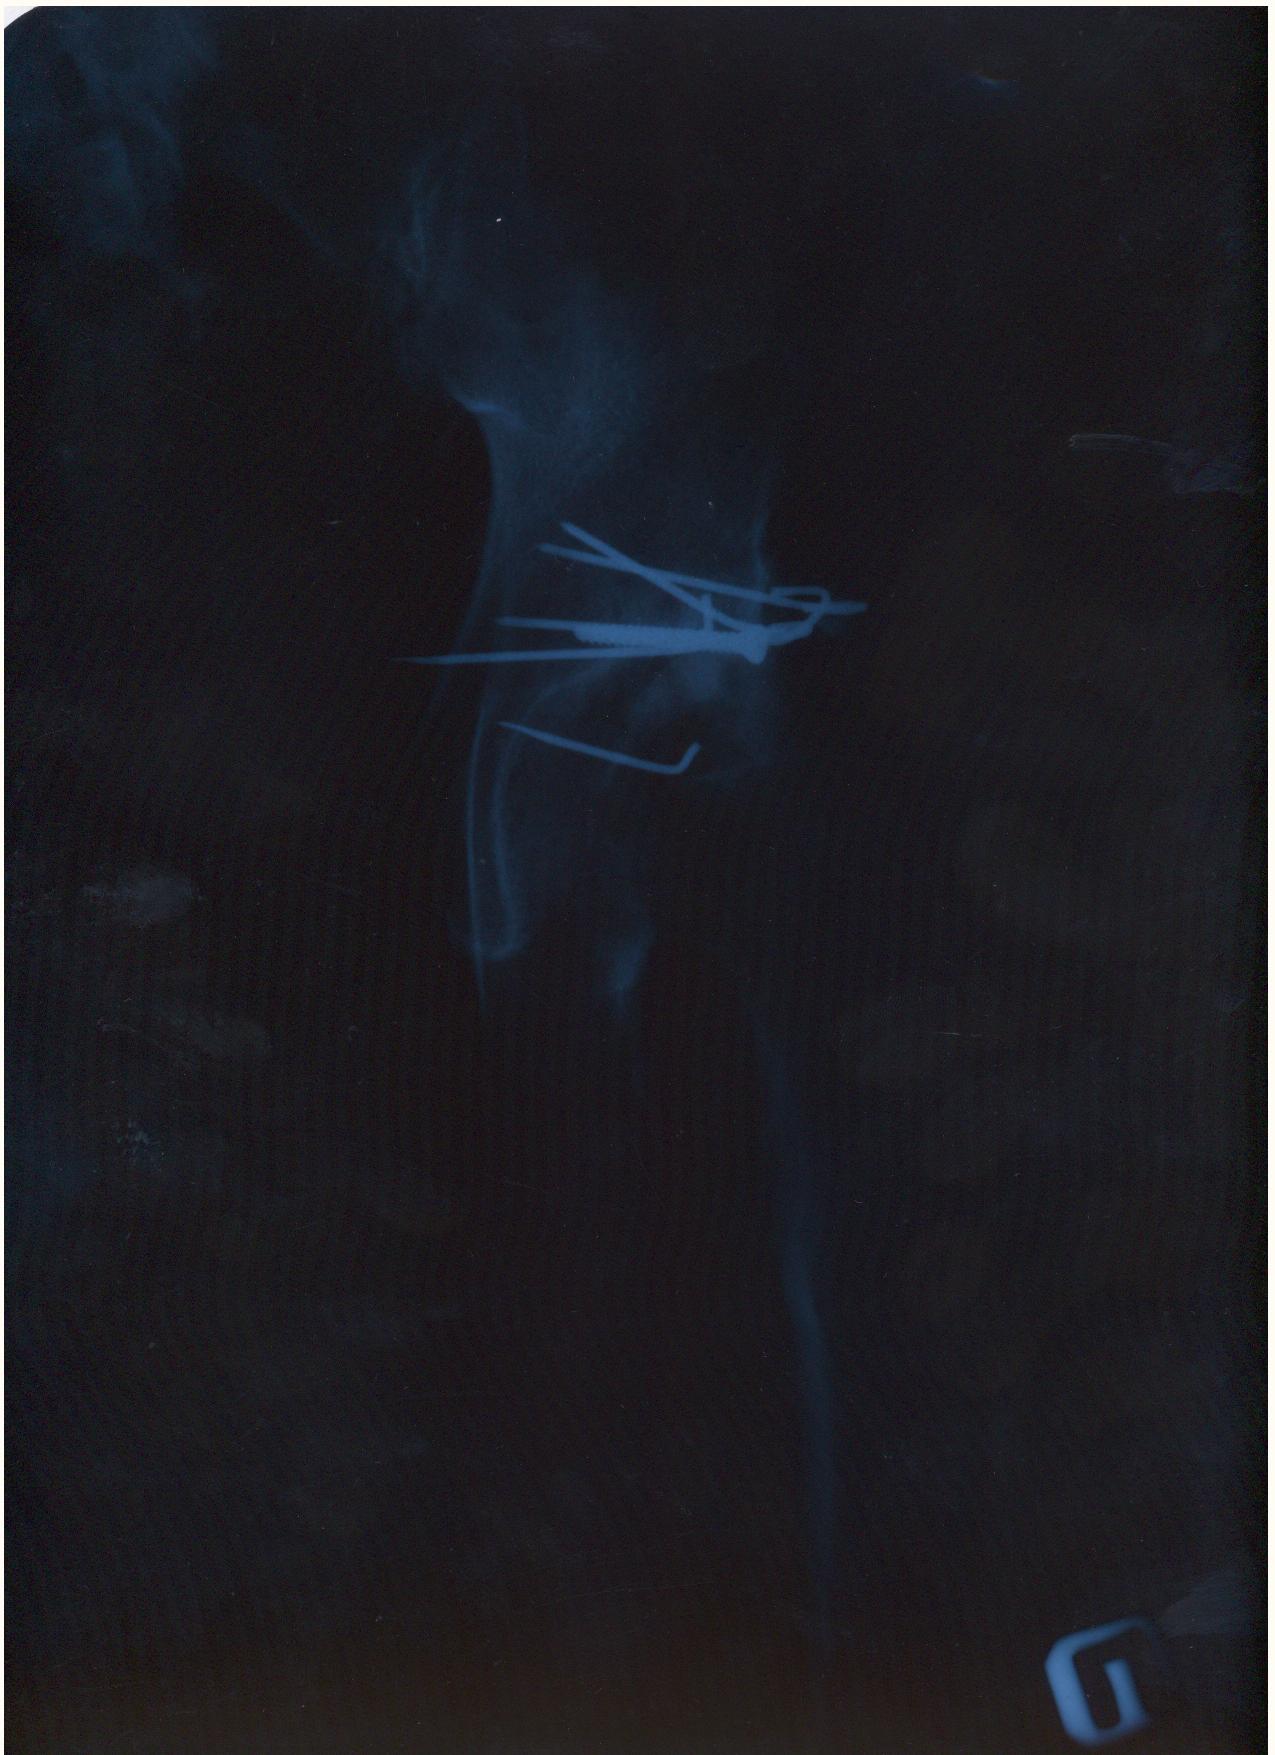

Мой товарищ попал в страшную аварию, виновник аварии как и два его пассажира погибли. Товарищ с пассажиром живы, но другу нужна сложная операция. Мы не можем никак найти врача способного прооперировать бедренный сустав, в пироговке отказали. Парню всего 30 лет всеми силами пытаемся поставить на ноги. выкладываю выписки и документы, могу выслать архивом на почту или привезти куда скажите.